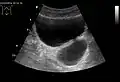

Diverticulum of the urinary bladder of a 59-year-old man, transverse plane

Bladder diverticula containing stones: the bladder wall is thickened due to possible transitional cell carcinoma.- Bladder diverticula as seen on ultrasound with doppler[18]

- Bladder diverticula as seen on ultrasound[18]